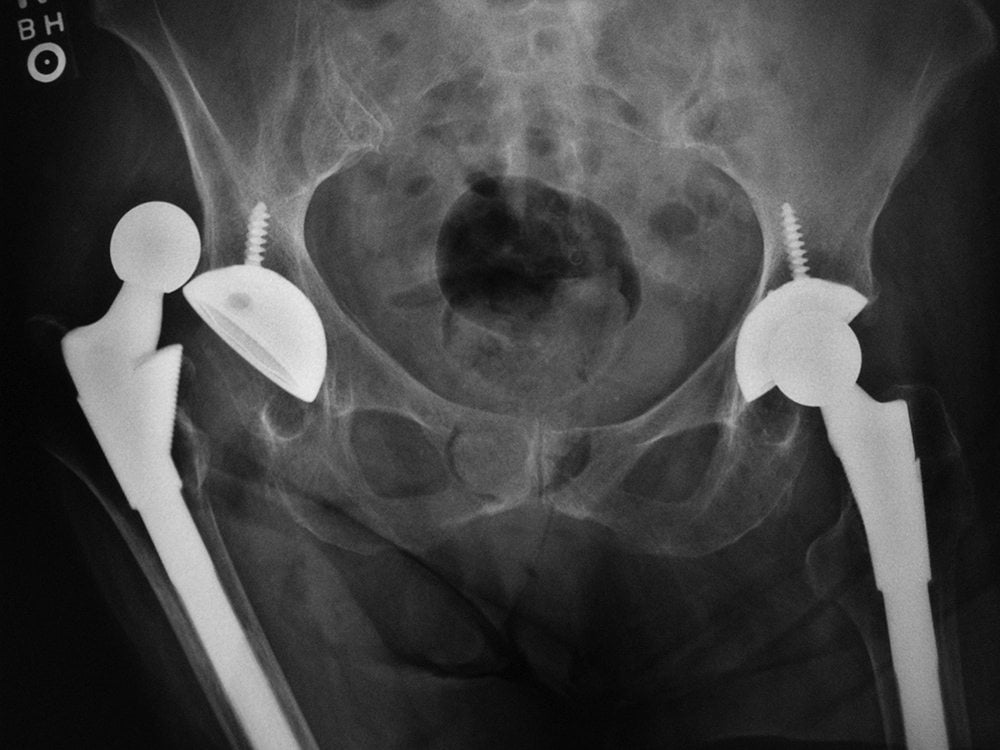

Назначается эндопротезирование ТБС, как процедура замены разрушенных частей либо полной имплантации и замены родного сустава пациента на искусственный.

Терапия коксартроза третьей степени заключается в применении хирургического вмешательства — эндопротезирования. Схематично операцию можно описать так:

- пациента вводят в наркоз, возможно применение спинальной анестезии;

- далее ортопед-хирург проводит разрез мягких тканей в области бедра до самой кости;

- следующий шаг — иссечение пораженной ткани и установка протеза.

Как и при 3 степени, здесь необходимо оперативное вмешательство с полной заменой разрушенного сочленения на искусственный. Такая конструкция полностью имитирует родное сочленение и помогает вернуться к полноценной жизни.